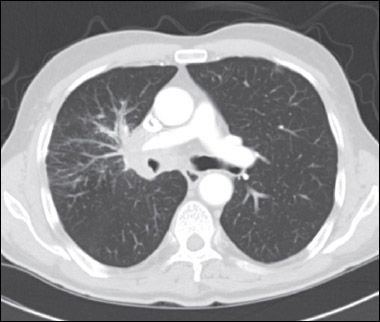

A CT scan of the chest showed an amorphous soft tissue mass that encased and constricted the right main pulmonary artery and the right main stem bronchus (A). Extensive round masses were visible in the liver; the largest mass was in the right medial hepatic lobe and measured 2.7 × 2.4 cm (B).

SCLC typically presents as a large central mass (as in this patient) with mediastinal adenopathy. SCLC can infiltrate the submucosa, causing either intrinsic or extrinsic compression of the bronchi. SCLC has a propensity for spreading to the liver, brain, bone, and bone marrow. The neutropenia and thrombocytopenia seen in this man can be explained by the infiltration of his bone marrow by the SCLC. In a series of 129 patients with SCLC, 30% had bone marrow involvement. However, in only 2.3% was the bone marrow the only site of metastatic disease.7 Other presenting symptoms include cough, dyspnea, hemoptysis, chest pain, postobstructive pneumonia, and the paraneoplastic syndromes mentioned above.